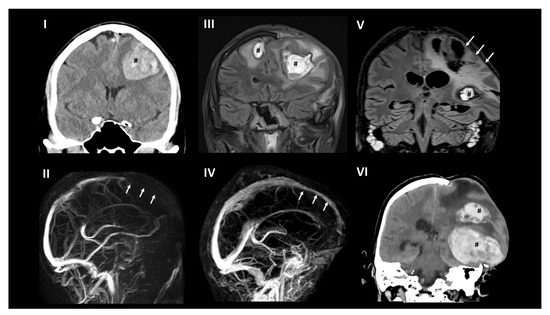

2. Case Report

3. Brain Imaging